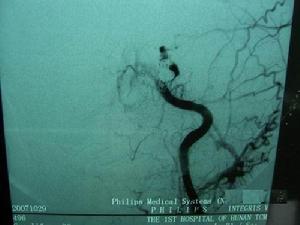

外傷性頸內動脈海綿竇瘺CT圖因此,常須採用股動脈插管行全腦選擇性血管造影 除了對患側頸內、頸外動脈造影之外,還要在壓迫患側頸動脈,暫時阻斷血流的情況下,拍攝對側頸內動脈和椎動脈造影像 通常在患側頸內動脈造影像上,只見海綿竇內一團造影劑陰影 遠端腦血管充盈較差 瘺口的確切部位難以確定。採用椎動脈造影同時壓迫患側頸動脈,使造影劑由後交通支逆行經頸內動脈海綿竇瘺口溢出,則往往清晰可見。同時行健側頸內動脈造影也可了解Willis環是否完整,估計腦動脈代償情況,有助於判斷患側頸內動脈血流是否可以中斷 另外,通過選擇性頸外動脈造影能顯示有無頸內動脈的分支與海綿竇底部腦膜中動脈、腦膜副動脈及咽升動脈相吻合,形成頸外動脈供血。Parkinson(1967)曾將外傷性頸內動脈海綿竇瘺分為兩類:其一,為海綿竇段頸內動脈本身破裂所致;其二,為海綿竇段頸內動脈的分支斷裂所引起。後者採用單純球囊栓塞常難以奏效。

腦血管造影可顯示頸內動脈、海綿竇、大腦中靜脈、蝶頂竇或眼靜脈明顯擴張。病側大腦前、大腦中動脈顯影不良。病變對側造影常顯示雙側大腦前及大腦中動脈充盈。